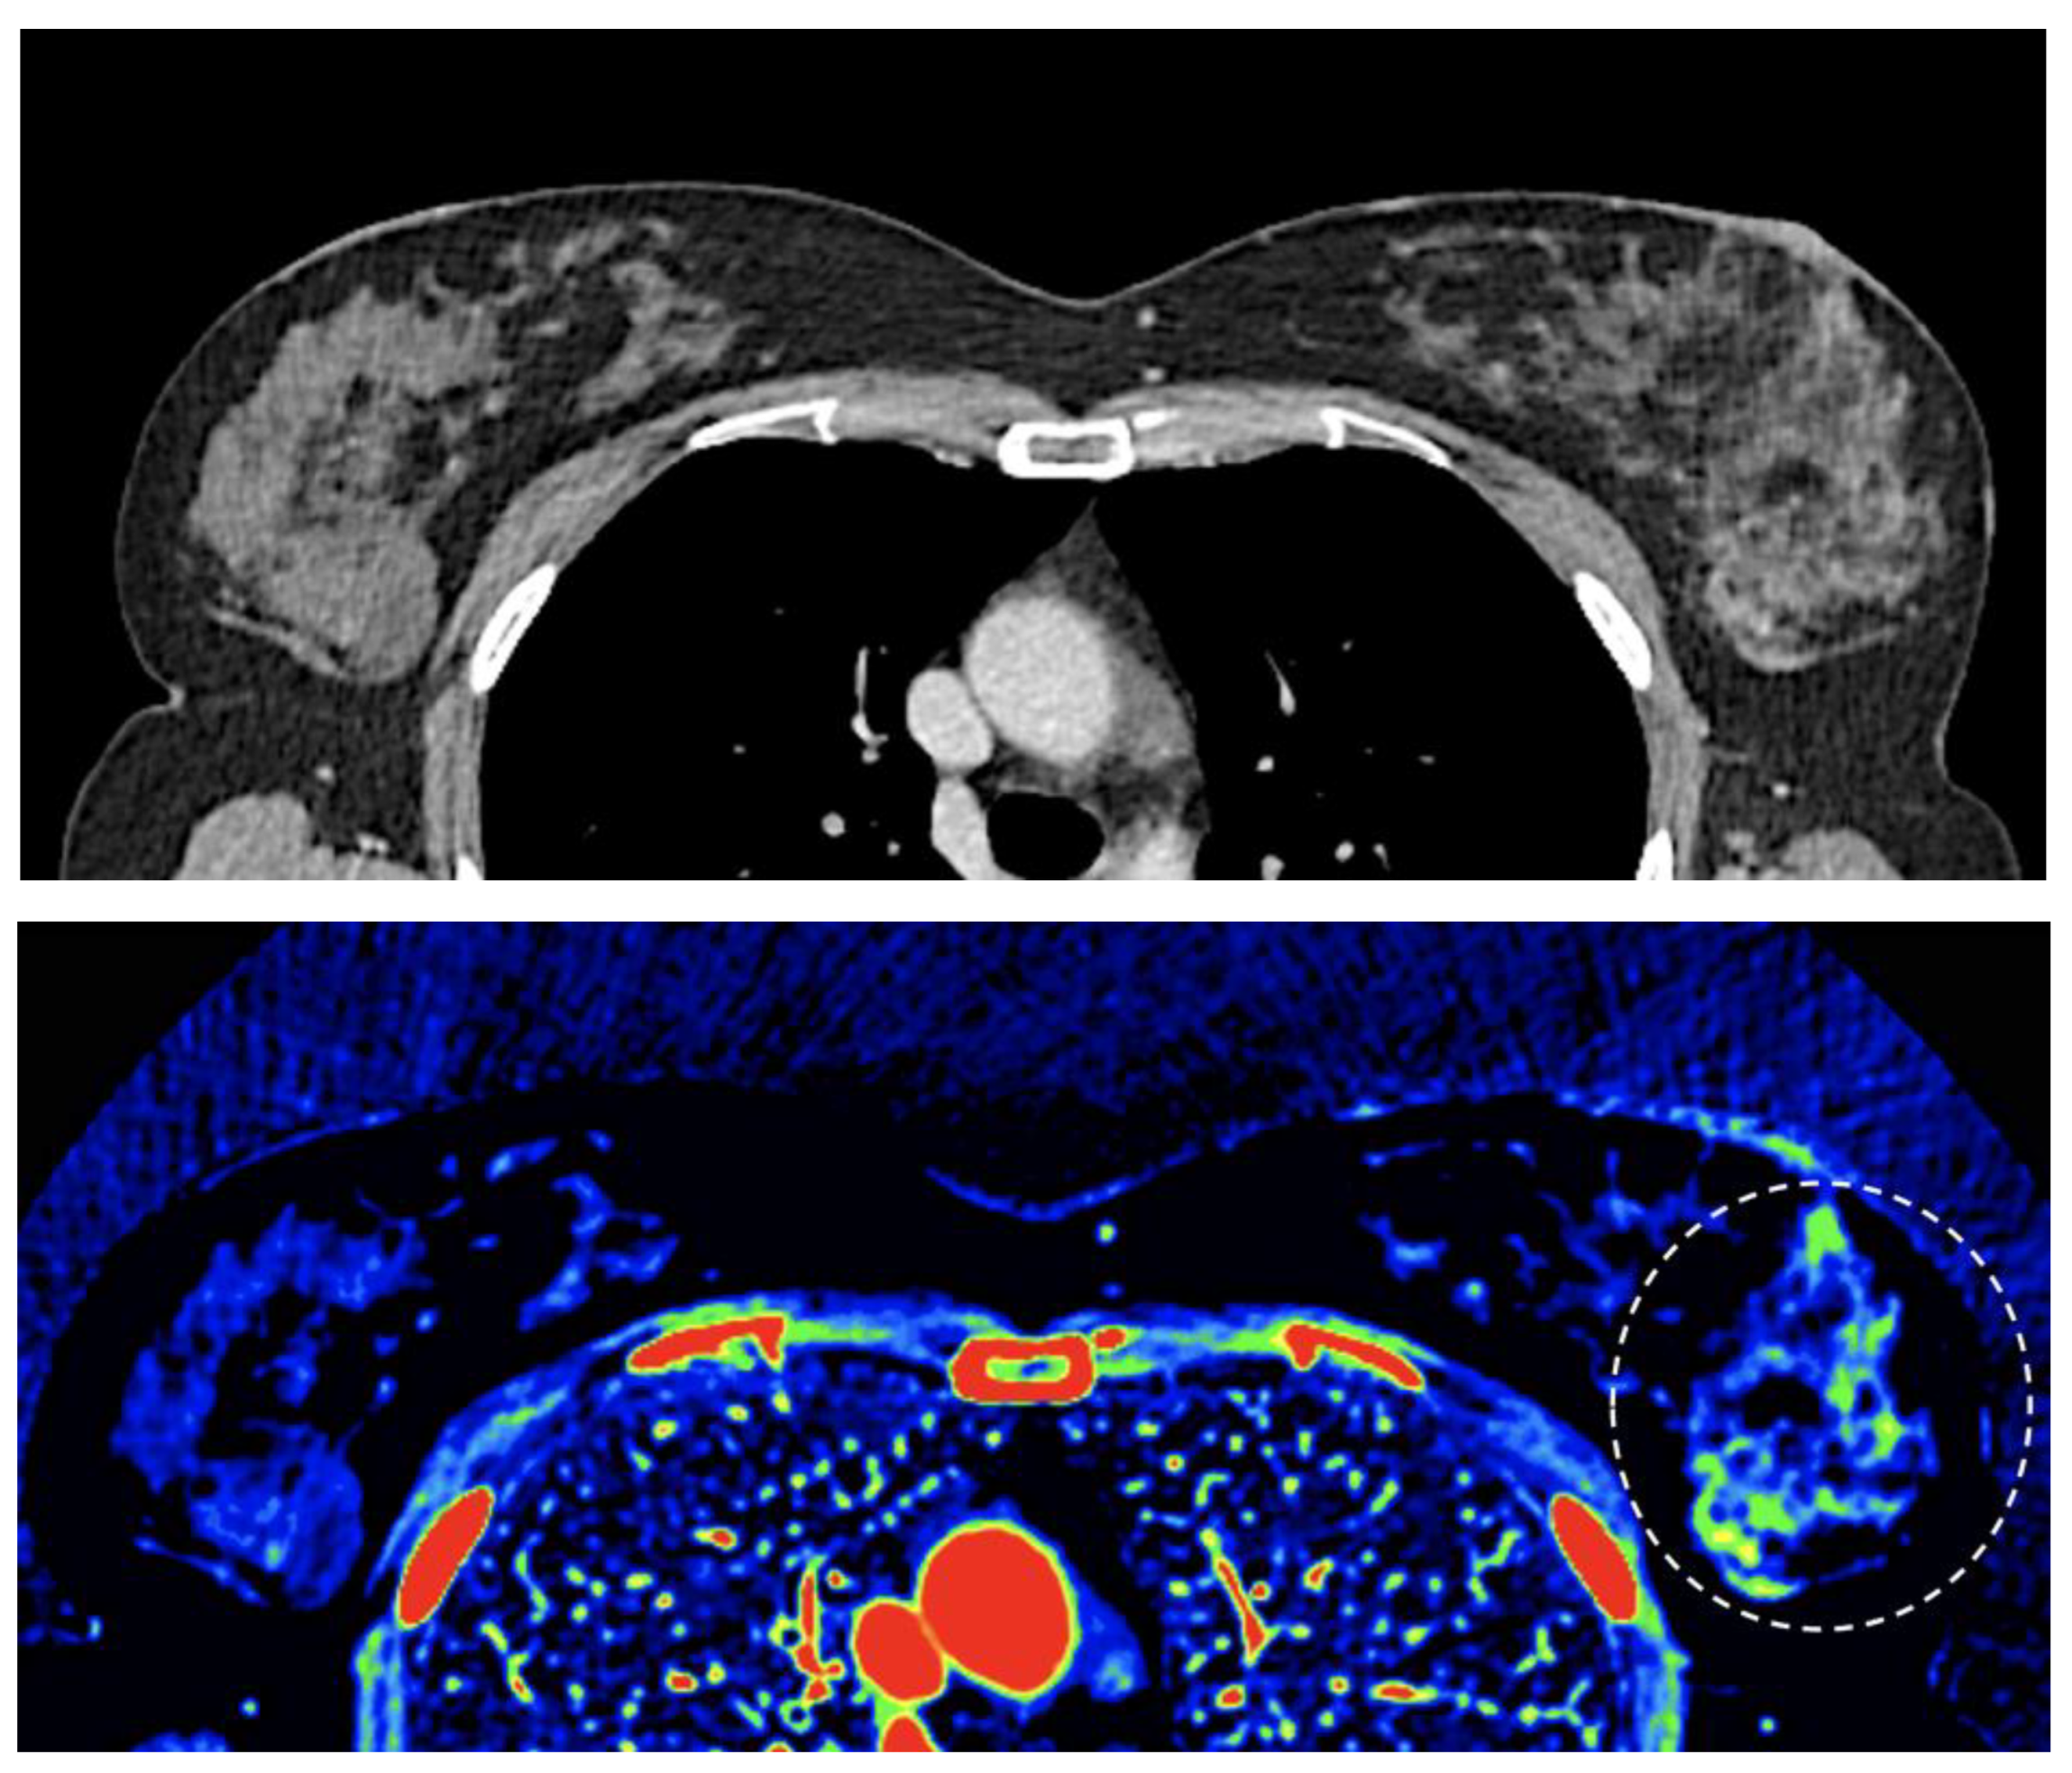

- Breast imaging. DECT seems to be a reliable tool for diagnosis and locoregional staging of breast cancer [36,37,38,39,40] [Figure 12]. Klein, et al [37] found robust cut points for the differentiation of benign and malignant lesions (Zeff < 7.7, iodine content of <0.8 mg/ml). The DECT quantitative parameters may also be useful in predicting breast cancer invasiveness and histopathological and molecular subtypes of breast tumors. In the case of node-staging, the similarity of quantitative DECT parameters between the primary lesion and axillary LNs may predict axillary metastasis in breast cancer [40,41].